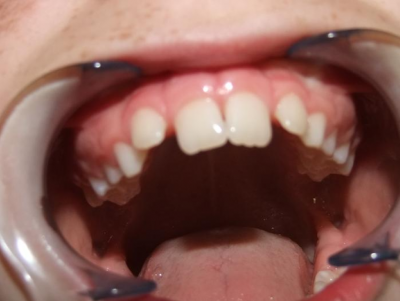

eindfoto

Leeftijd bij aanvang: 9 jaar

1-6 Bonded Hyrax + partieel vast onderkaak + TransForce onderkaak

7-13 Twinblock

13-22 volledig vast onder- en bovenkaak + rotator

Retentie: wrap en c-c bar

Leeftijd bij retentie: 12 jaar